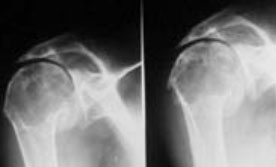

Prothèse totale d’épaule (PTE)

L’indication principale à la mise en place d’une prothèse totale d’épaule (PTE) est l’omarthrose primitive ou secondaire. Il s’agit d’une destruction progressive du cartilage de l’articulation gléno-humérale. A ces indications, nous pouvons également ajouter les ostéonécroses de la tête humérale, les omarthroses centrées ou excentrées, les fractures et séquelles traumatiques par exemple, les indications sont nombreuses. La prise en charge chirurgicale est basée principalement sur des arguments cliniques :

Le Docteur Andrin réalisera au cours d’une consultation un examen clinique complet, et prescrira un bilan radiographique. A l’issue de ces examens, l’indication chirurgicale sera discutée avec le patient, et les modalités et complications possibles seront expliquées précisément.